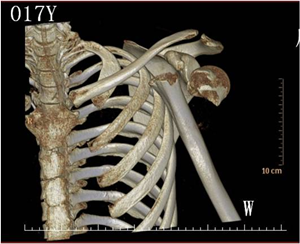

▲术前 左侧肱骨颈(上臂骨)骨折伴肩关节脱位